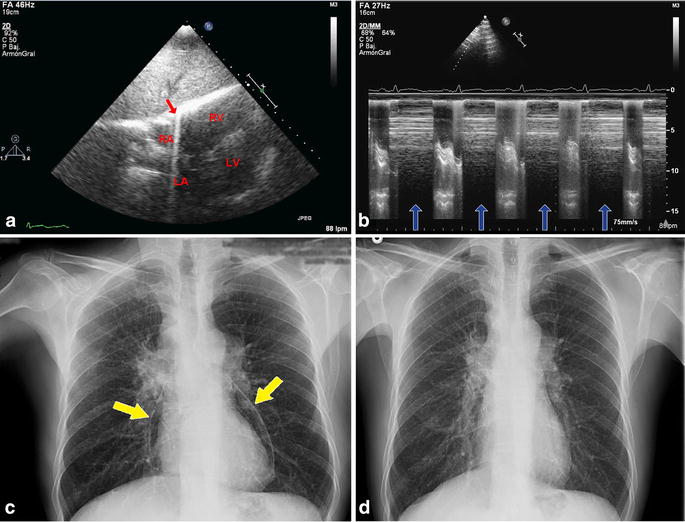

A 55-year-old male who was a heavy smoker was admitted to the emergency department. He presented with a 1-month history of productive cough and pleuritic chest pain. A thorough study was performed, leading to the diagnosis of small-cell lung carcinoma with metastasic disease. Pericardial effusion was noted in a thorax computed tomography scan. A transthoracic echocardiogram confirmed the presence of pericardial effusion with diastolic collapse of the right ventricle and both atria as signs of cardiac tamponade. The patient underwent pericardiocentesis and 600 ml of serohematic fluid was obtained. Pericardial drainage was removed after 3 days, and the patient remained asymptomatic. A second echocardiogram was then performed, but the two-dimensional acquisitions could not be properly assessed due to an imaging artifact. The subcostal view showed spontaneous pericardial echoes and the M-mode indicated that these were related to the cardiac cycle (Fig. 1a, b). These findings suggested the presence of air within the pericardial sac, a condition known as pneumopericardium. This diagnosis was later confirmed on chest radiography, which revealed the presence of the “halo sign” (Fig. 1c). Since the patient was asymptomatic, a conservative approach was taken: radiographic control after 1 week showed pneumopericardium resolution (Fig. 1d).

a Transthoracic echocardiogram in the subcostal view. Notice the spontaneous echoes resembling “comet tails” (red arrow) that are the result of the presence of air within the pericadial sac. RV Right ventricle, LV left ventricle, RA right atrium, LA left atrium. b M-mode shows that the artifact (blue arrows) is related to the cardiac cycle. c Chest radiography. Notice the radiolucent band around the heart siluet (“halo sign”, yellow arrows). d Control chest radiography after 1 week shows pneumopericardium resolution